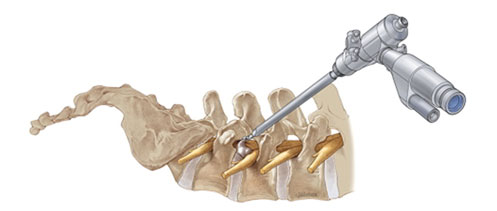

• Laminectomy: Increasing the space in the spine canal by removing the bone plate present on the vertebra (laminae).

• Laminotomy: a portion of the arch on the vertebra is removed.

• Foraminotomy: Removal of obstruction from nerve root.